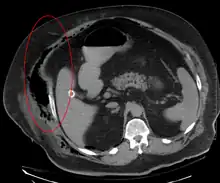

Medical imaging

Imaging has a limited role in the diagnosis of necrotizing fasciitis. The time delay in performing imaging is a major concern. Plain radiography may show subcutaneous emphysema (gas in the subcutaneous tissue), which is strongly suggestive of necrotizing changes, but it is not sensitive enough to detect all the cases, because necrotizing skin infections caused by bacteria other than clostridial infections usually do not show subcutaneous emphysema. If the diagnosis is still in doubt, computed tomography (CT) scans and magnetic resonance imaging (MRI) are more sensitive modalities than plain radiography. However, both the CT scan and MRI are not sensitive enough to rule out necrotizing changes completely.[2] CT scan may show fascial thickening, edema, subcutaneous gas, and abscess formation.[2] In MRI, when fluid collection with deep fascia involvement occurs, thickening or enhancement with contrast injection, necrotizing fasciitis should be strongly suspected. Meanwhile, ultrasonography can show superficial abscess formation, but is not sensitive enough to diagnose necrotizing fasciitis.[2] CT scan is able to detect about 80% of cases, while MRI may pick up slightly more.[14]